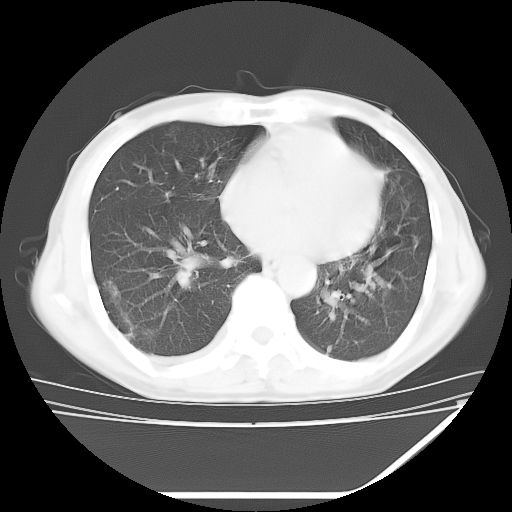

男,59岁,“结核性胸膜炎”30余年,胸部经常疼痛,多次x检查提示“肺部”炎症。腹部疼痛5日,b超提示:“肝内短管结石,余显示不清,建议进一步检查。”

两肺结核并右侧胸腔积液;脾脏、腹腔及腹膜后淋巴结结核[陈旧性];肝内胆管结石

胸部腹部都是结核(双肺。纵隔淋巴结,肝脏,脾脏,肠系膜)

两肺结核并右侧胸腔积液;脾脏、腹腔及腹膜后淋巴结结核[陈旧性];肝内胆管结石。直肠息肉?

结核,是血行播散还是淋巴?